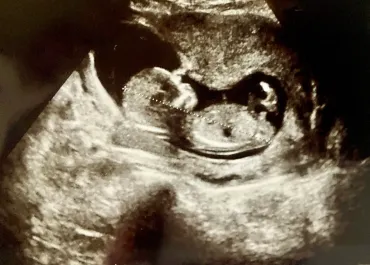

4Dエコーは、赤ちゃんの様子を立体的に、リアルタイムの動画で見ることができる検査です。

赤ちゃんの表情や動きを観察できるのが特徴です。

4Dエコーは、3Dエコーに時間の要素を加えたもので、リアルタイムで動いている赤ちゃんの立体映像を観察できます。

これにより、胎動や表情の変化を動画で確認できます。

4Dエコーでは、あくびや指しゃぶりをする赤ちゃんの仕草や表情も観察できますが、赤ちゃんの位置や体勢によっては顔が見えない場合もあります。